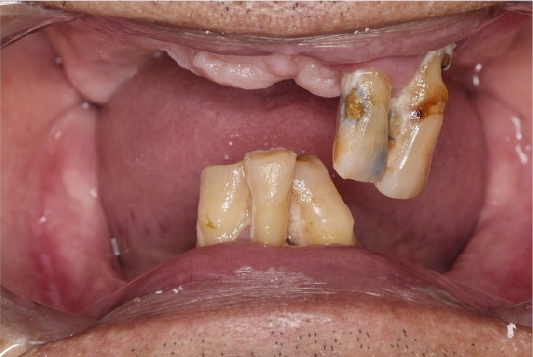

CASE02

■ 治療内容

上顎オールオン4インプラント治療(4本頬骨インプラント)

■ 治療費用

(モニター)3,330,000円(税込)

■ 治療期間

約10ヶ月

■ リスク

治療後の腫れや出血、またメンテナンスを怠ることで周囲炎のリスクあります。